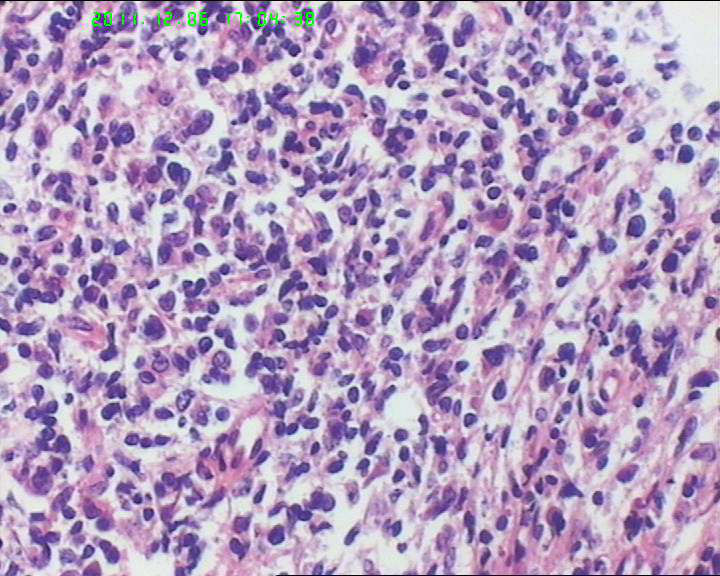

53岁女性患者,鼻腔肿物,中线恶网?韦格尔肉芽肿?

患者流脓涕1年,加重1月。左鼻腔息肉样增生物,质软,易出血。

送检灰白色绿豆大组织4块。

组织内见大量形态各异的异型明显的细胞,弥漫分布,背景见肿瘤素质,首先考虑结外NK/T细胞淋巴瘤,鼻型;恶黑待排。